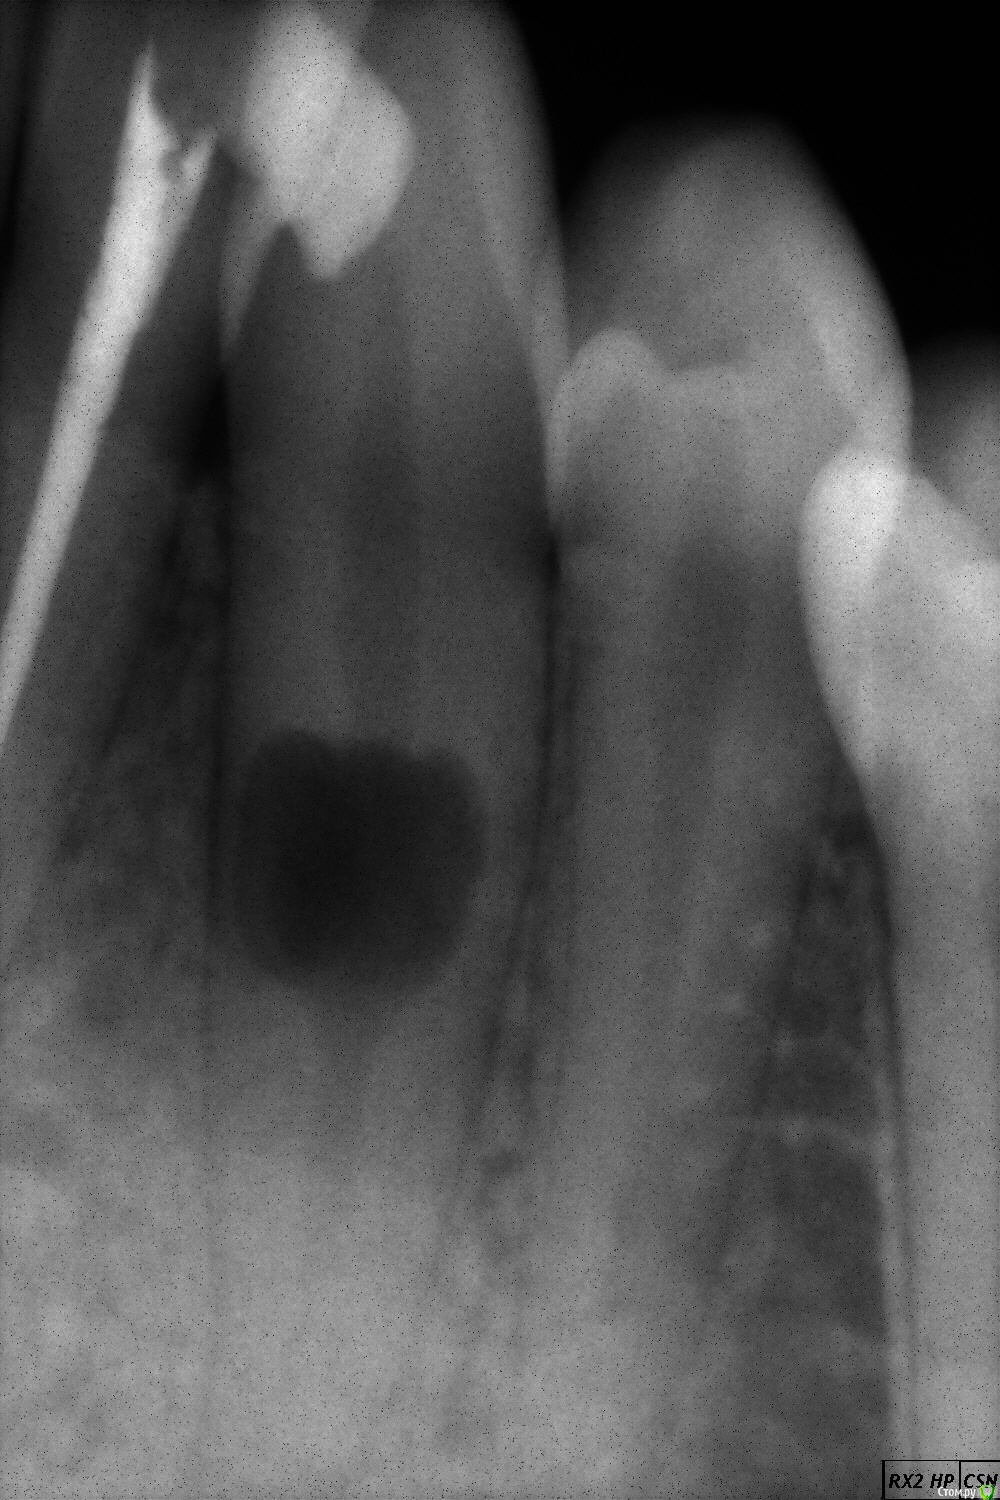

Юл1. Опубликовано 19 мая, 2020 Поделиться Опубликовано 19 мая, 2020 Здраствуйте, в хирургии была тема, но хотелось бы ещё мнения послушать. Случайно обнаружили в феврале этого года такой зуб, клиник много посетила, никто лечить не берёт. Две недели назад образовался прыщик, лопнул вчера, сейчас нет ничего, мазала метрогилом и полоскала хлоргексидином. Кт делала, ничего там особенного нет, не могу показать, не умею. Зуб абсолютно не болит. Интересует что это за прыщик был? Свищ? Бессимптомный периодонтит? Спасать зуб не буду, все в один голос говорят что шансов нет лезть в канал. Буду удалять если сломается. Вот что тогда делать? Имплант не встанет, брекеты финансово не смогу поставить, мост не хочу. Есть ли ещё какие варианты протезирования пусть даже не очень надёжного? Ссылка на комментарий

St. Опубликовано 19 мая, 2020 Поделиться Опубликовано 19 мая, 2020 Спасать зуб не буду, все в один голос говорят что шансов нет лезть в канал Учитывая вашу скученность зубов, я бы спасала. Шанс не очень высокий, но продлить зубу жизнь можно. Интересует что это за прыщик был? Свищ? Да Ссылка на комментарий

Дмитрий Л. Опубликовано 19 мая, 2020 Поделиться Опубликовано 19 мая, 2020 Лечить нужно, ле-чить. Ссылка на комментарий